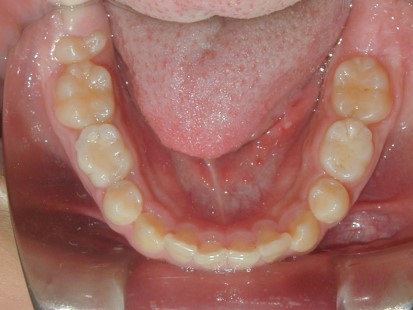

永久歯に交換するためのスペース不足による前歯のガタガタで、取り外しができる拡大床にて上下顎の幅を拡大した後、上顎の前歯をマルチブラケット装置で並べました。治療の期間は1年9か月でした。

初診時